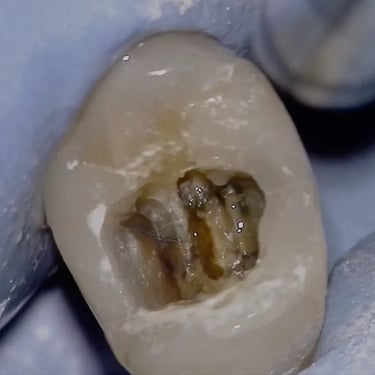

Pulpitis Crónica Hiperplásica

La pulpitis crónica hiperplásica es una inflamación de la pulpa con crecimiento excesivo de tejido pulpar a través de una caries abierta.

Los pacientes notan un tejido rojo que sobresale de la cavidad dental.

El tratamiento incluye la eliminación del tejido afectado y un tratamiento de conducto. Es crucial tratar la caries para evitar infecciones adicionales.